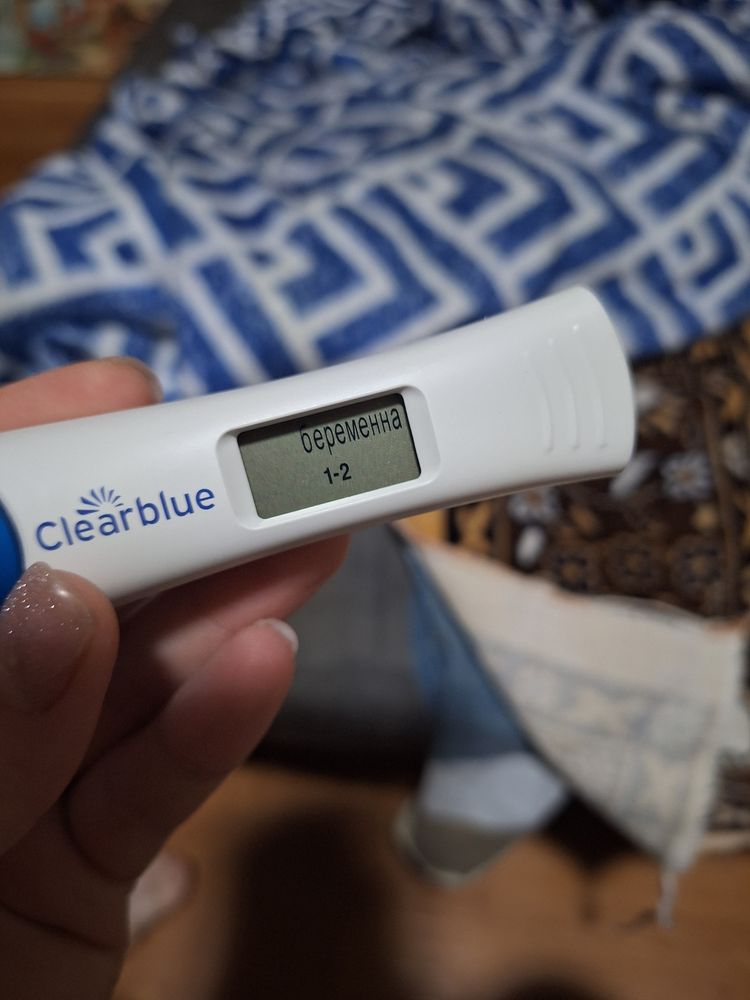

Здравствуйте. У меня такая ситуация. 3 день задержки месячных , с мужем планировали беременность (вторая уже) , тесты положительные , так же делала электронный показал беременность 1-2 недели , пришла сегодня на узи ничего не нашли. Если посчитать срок от первого дня последних месячных то уже 5 недель 0 дней. Почему так? Узист сказала сдавать кровь на хгч каждые 2 дня и придти через 10 дней на узи. Вот переживаю вдруг внематочная , или замершая.